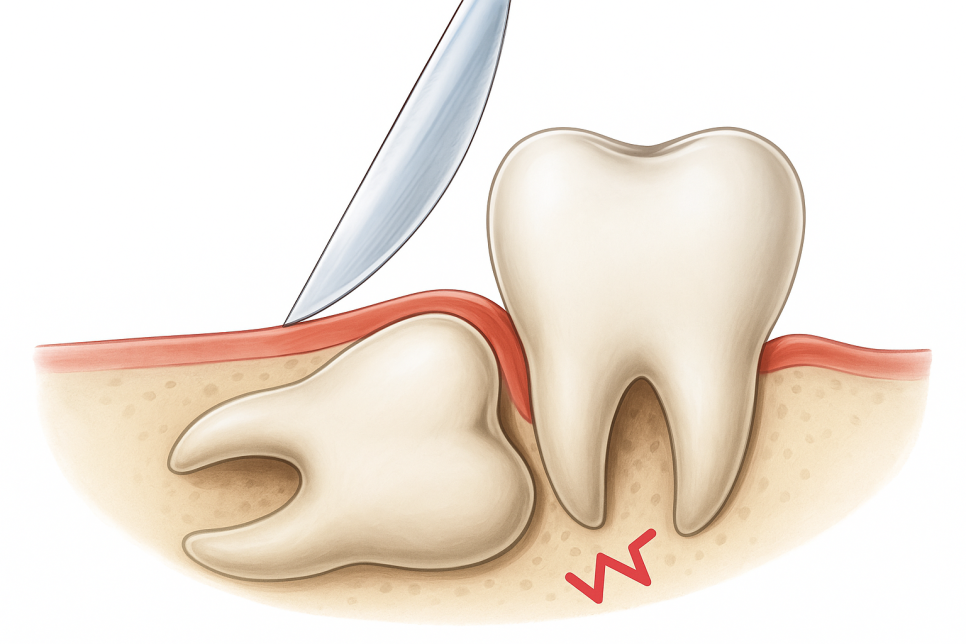

아래턱에 위치할 때는

위턱보다 뿌리 형태가

복잡한 경우가 많아 상대적으로

긴 시간이 필요합니다.

신경관과의 거리를 고려하여

신중한 접근이 필요한 부위이며,

특히 왼쪽 아래의 경우

매복 사랑니 일 때가 많아

외과적 절개 과정이 필요할 수 있습니다.